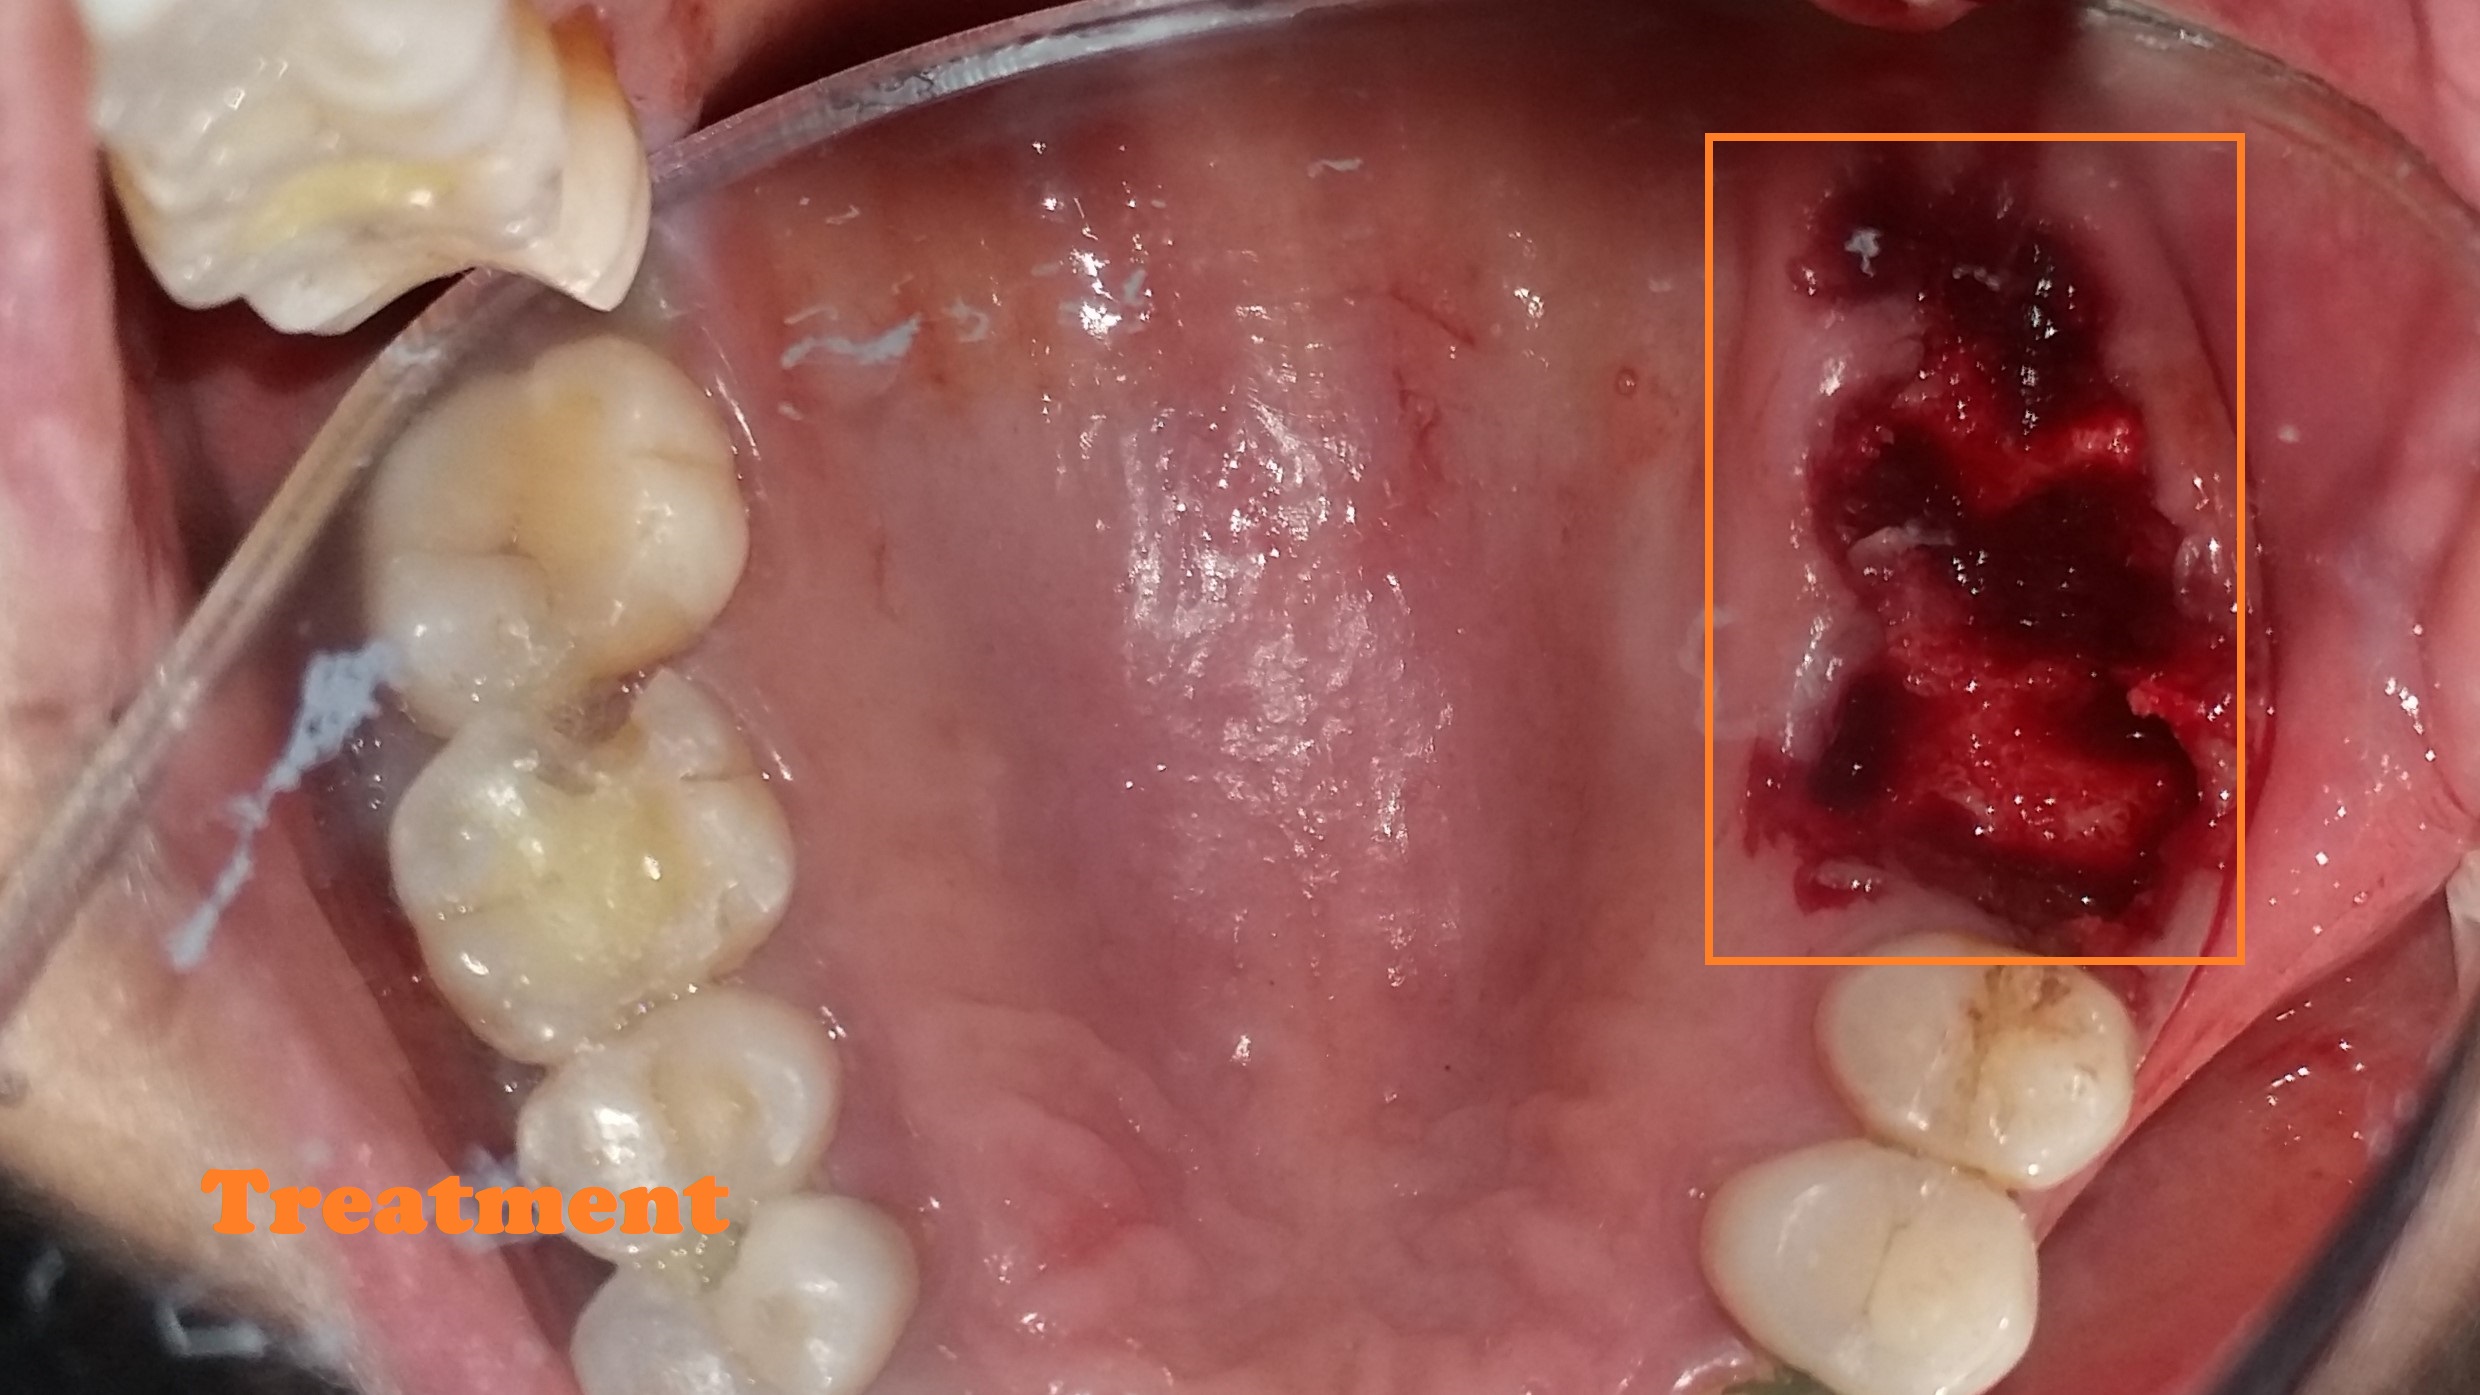

Root Canal Treatment

- Removes infected nerve tissue while preserving your natural tooth.

- Relieves pain, swelling, and sensitivity caused by deep decay or infection.

- Protects against tooth extraction and maintains natural biting ability.